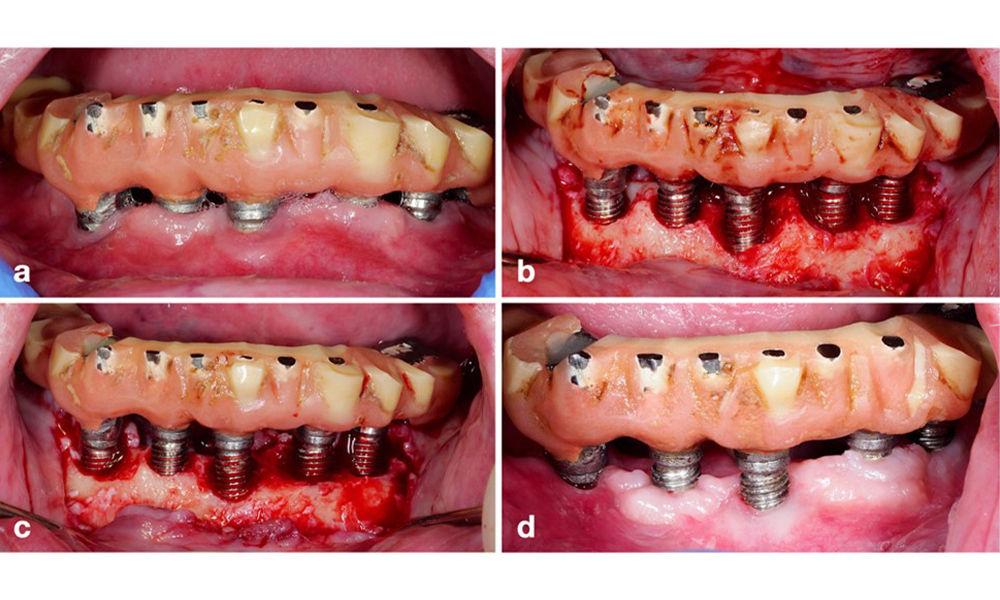

Peri-implantitis is identified by (1) signs of inflammation similar to mucositis, (2) radiographic evidence of bone loss after initial healing and (3) an increase in probing depth compared to measurements taken shortly after placing the prosthetic reconstruction (figure 2). In the absence of previous radiographs, radiographic bone level of ≥ 3 mm along with bleeding on probing and probing depths ≥ 6 mm, indicates peri‐implantitis.

Full-arch restoration with peri-implantitis of varying degrees at some implants. The implant in position 21 is severely affected with probing depths up to 9 mm (a), bleeding on probing, and suppuration from the peri-implant sulcus and a vestibular fistula (b–c); the radiograph shows approximately 50 % bone loss for the implant with peri-implantitis in position 21, while the implant in position 23 shows limited bone loss, corresponding approximately to what can be expected after initial healing for this type of implants (d).

Figure 2. Full-arch restoration with peri-implantitis of varying degrees at some implants. The implant in position 21 is severely affected with probing depths up to 9 mm (a), bleeding on probing, and suppuration from the peri-implant sulcus and a vestibular fistula (b–c); the radiograph shows approximately 50 % bone loss for the implant with peri-implantitis in position 21, while the implant in position 23 shows limited bone loss, corresponding approximately to what can be expected after initial healing for this type of implants (d).

The expected bone loss after initial healing attributed to marginal bone remodelling, varies based on factors such as the implant system or type. For instance, 1–2 mm bone loss is generally considered “normal” for bone level implants with an external connection (figure 2d, implant in position 23).